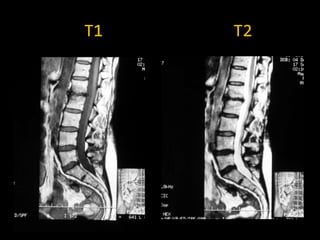

SECUENCIAS

 Secuencias T1: muy buena correspondencia

anatómica, pero poco sensibles a los cambios

patológicos

 Secuencias T2: muy sensibles a cambios patológicos,

pero no demuestran tan bien la anatomía. (requiere + tiempo)

 Como la mayoría de cambios patológicos son inflamatorios o

tumorales, comportan cambios de edema (aumento de agua

en los tejidos). Como en T2 agua es blanca, la mayoría de

lesiones serán hiper-intensas en T2

T1   T2